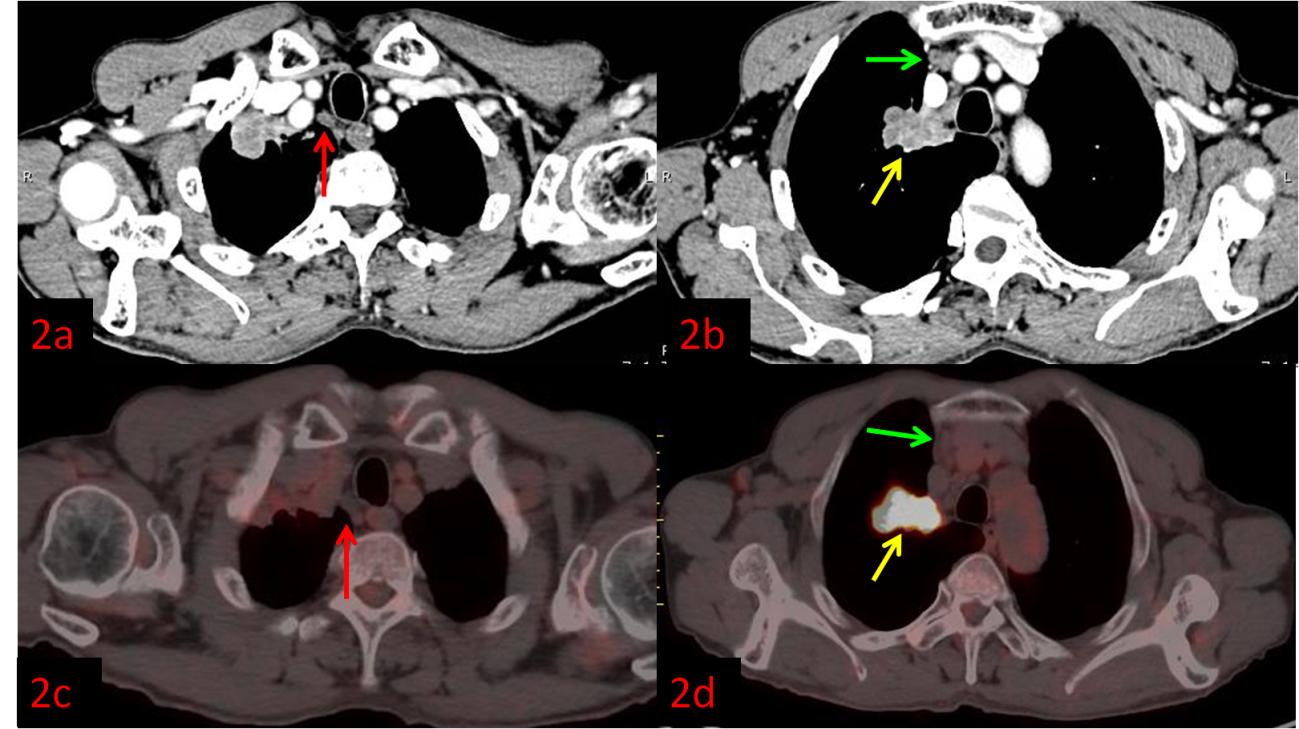

例2:老年男性,右肺上葉病變(黃箭)。強化CT示右上縱隔多發腫大淋巴結,不均勻強化,考慮轉移(圖2a紅箭、2b綠箭),初步分期為ⅢB,無法行手術根治。而PET/CT顯示淋巴結FDG代謝不高,考慮良性(圖2c紅、2d綠箭),患者分期降為ⅡB,于是進行了根治性手術。術后病理:右肺上葉鱗狀細胞癌,淋巴結均未見轉移。